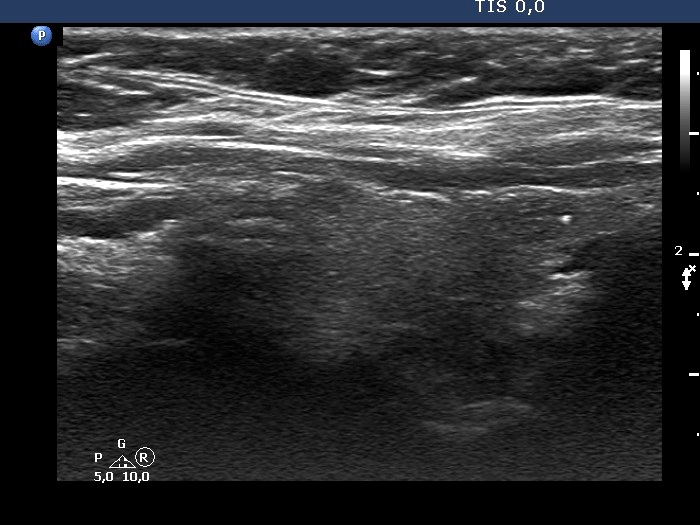

First examination (first row of images):

Clinical presentation: A 56-year-old woman known harboring an autonomously functioning adenoma requested a second opinion. The thyroid problem was known for more than ten years and caused neither hyperthyroidism nor problems. She underwent an ultrasound examination when she was told that her nodule is very suspicious because of the presence of microcalcifications.

Palpation: a not firm nodule in the left lobe.

Result of blood test: TSH 0.34 mIU/L, FT4 17.5 pM/L.

Ultrasonography. The thyroid was echonormal. There was a small hypoechogenic lesion in the right lobe while a nodular area in the left lobe. The latter had an upper, solid part and a lower, cystic part. The former presented echogenic granules and lines.Aspiration cytology was performed from the solid part and resulted in benign lesion.

Suggestion: yearly TSH determination, ultrasound in 4 years.